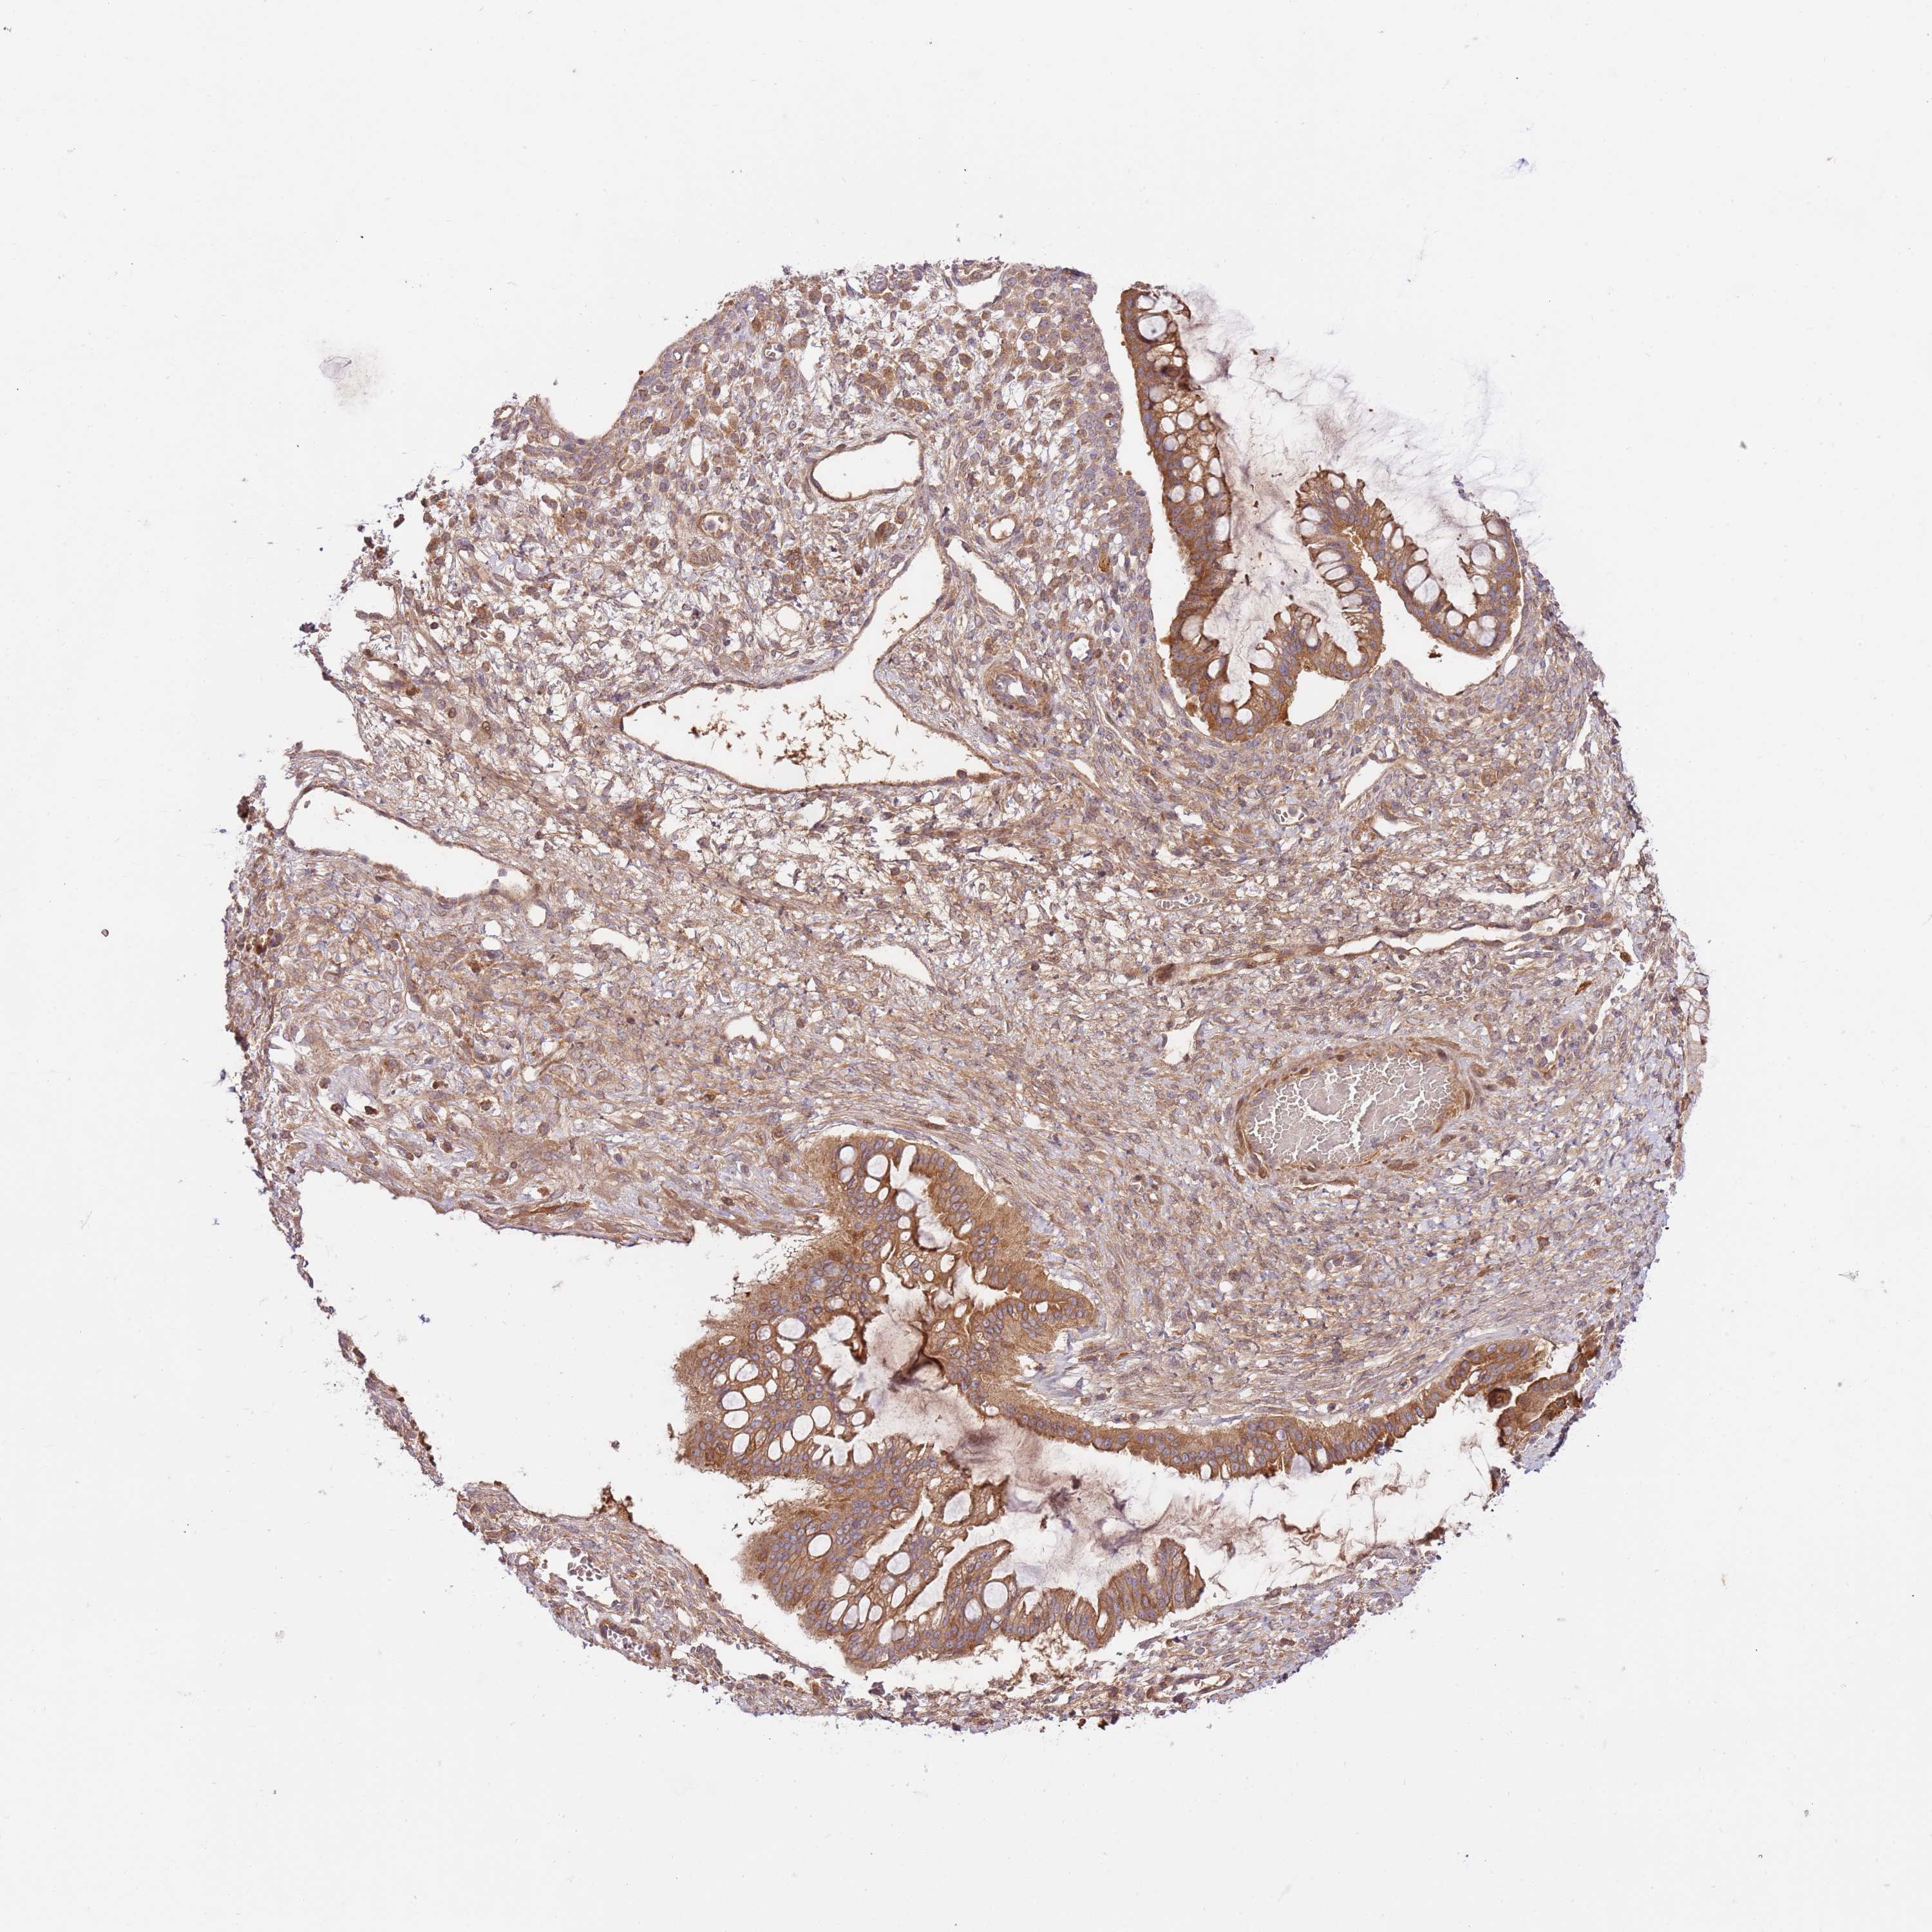

OVARIAN CANCER - Protein expressioni

A mouse-over function shows sample information and annotation data. Click on an image to view it in a full screen mode. Samples can be filtered based on level of antibody staining by selecting one or several of the following categories: high, medium, low and not detected. The assay and annotation is described here.

Note that samples used for immunohistochemistry by the Human Protein Atlas do not correspond to samples in the TCGA dataset.

Antibody stainingi

Antibody staining in the annotated cell types in the current human tissue is reported as not detected, low, medium, or high, based on conventional immunohistochemistry profiling in selected tissues. This score is based on the combination of the staining intensity and fraction of stained cells.

Each image is clickable and will lead to virtual microscopy that enables deeper exploration of all samples and also displays staining intensity scores, fraction scores and subcellular localization as well as patient and tissue information for each sample.

Antibody HPA046269

Staining

High

Medium

Low

Not detected

Intensity

Strong

Moderate

Weak

Negative

Quantity

>75%

75%-25%

<25%

None

Location

Nuclear

Cytoplasmic/membranous

Cytoplasmic/membranous,nuclear

Cystadenocarcinoma, serous, NOS

Carcinoma, NOS

Cystadenocarcinoma, mucinous, NOS

Carcinoma, endometroid